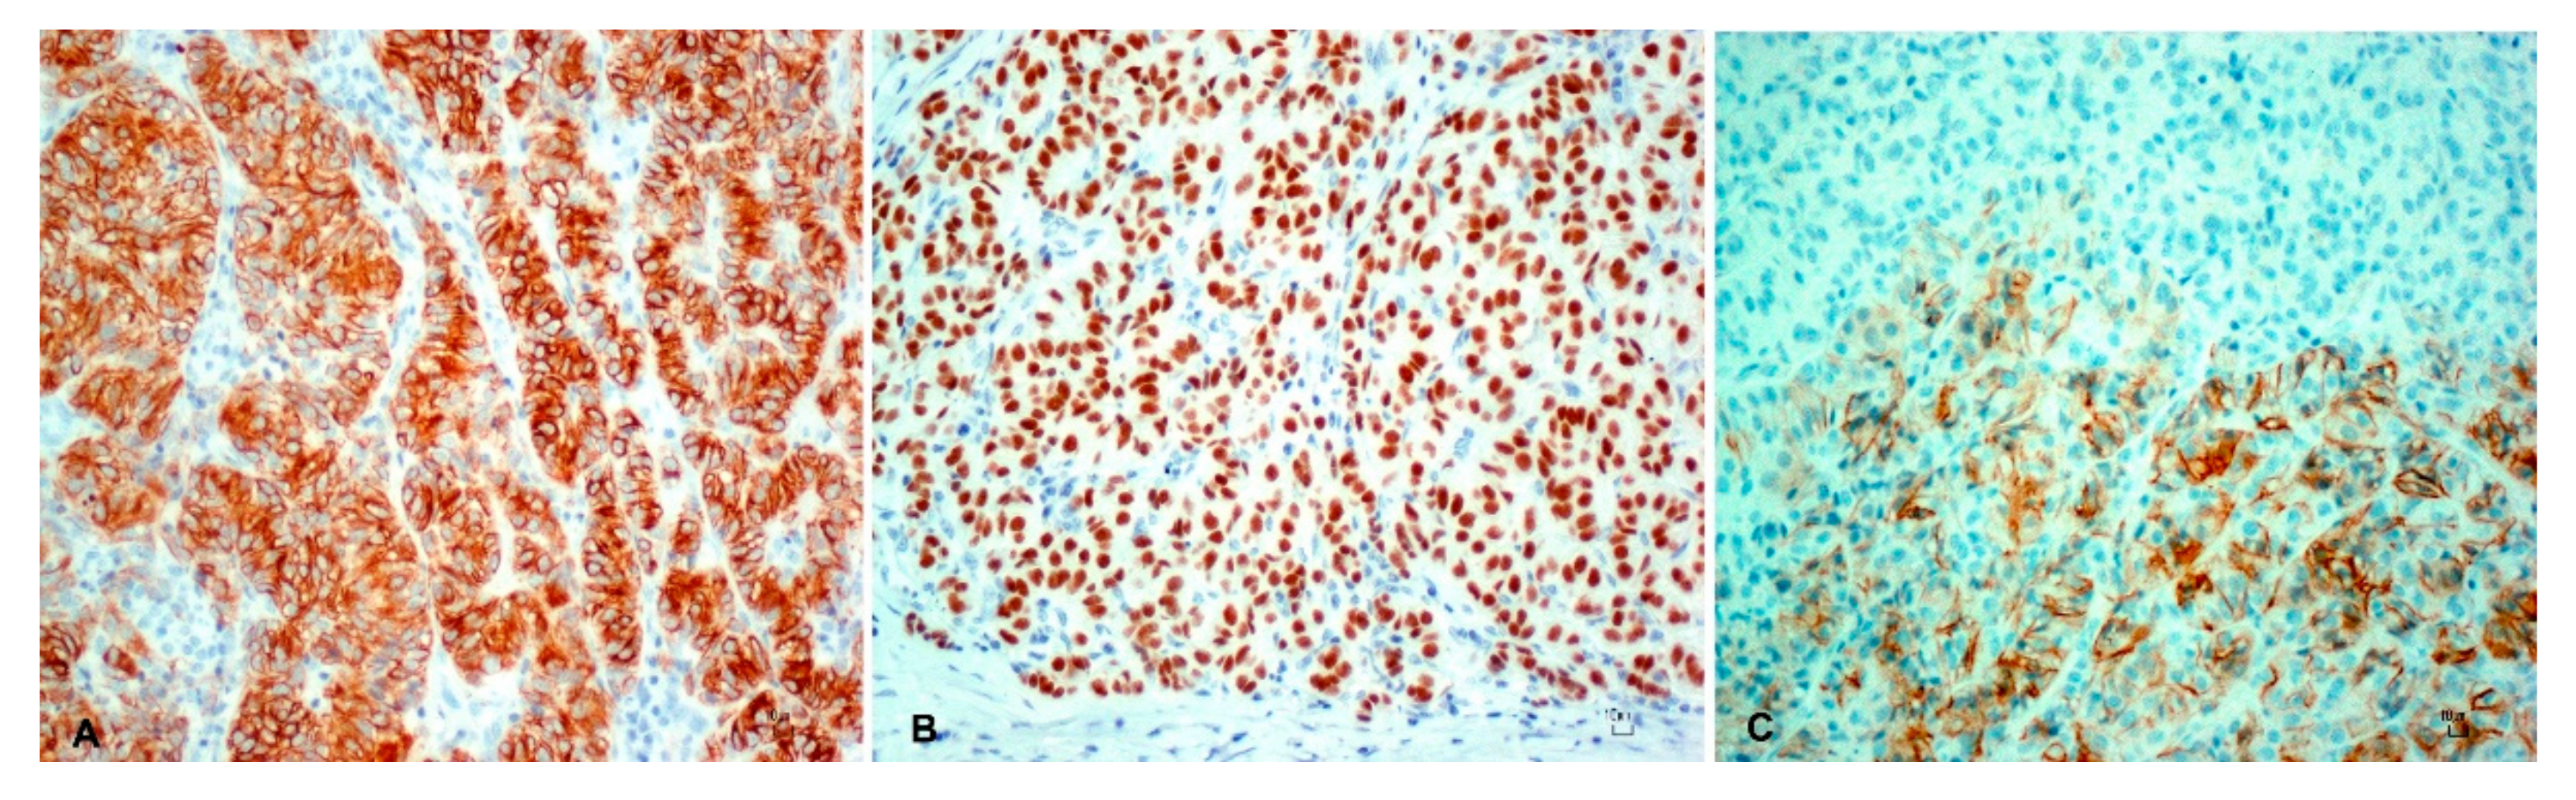

3. Results

| Tumor | CK AE1/AE3 | CK 34BE12 | CK 5/6 | p63 | KI-67 | CD56 | Melan-A |

| Trichoblastoma | ++ | ++ | ++ | ++ | + | + | − |